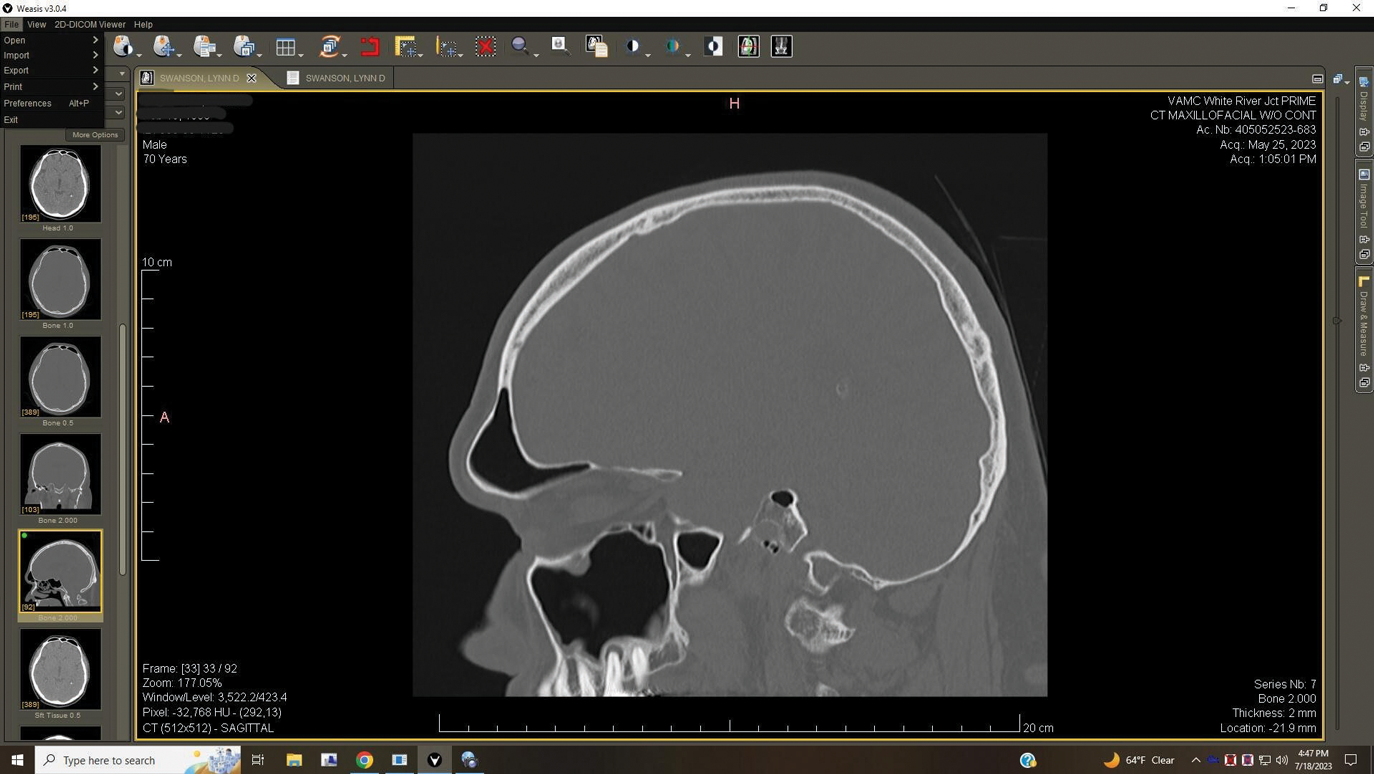

Fig 5. Case 2. Preoperative CT imaging from otolaryngologist showing periapical radiolucency associated with tooth No. 14 and associated maxillary sinus mucositis.

Figure 5

A 52-year-old male patient was seen by his otolaryngologist for symptomatic and unilateral sinusitis of 6 months duration. Medical CT showed dental pathology (Figure 5). His general dentist had a bitewing radiograph on file and referred the patient for endodontic evaluation (Figure 6).

As part of the endodontic evaluation, CBCT imaging showed periapical pathology associated with tooth No. 14 as well as significant MSEO (Figure 7 and Figure 8). Clinical testing confirmed the absence of a cold response but no tenderness to percussion or palpation. A composite buildup was in place, absent evidence of recurrent decay. Soft tissues were unremarkable.

The diagnosis for tooth No. 14 was pulpal necrosis with asymptomatic apical periodontitis. NSRCT was completed (Figure 9), followed by full-coverage restorative care performed by the general dentist. A 3-month follow-up revealed resolution of prior sinus symptoms, normal clinical findings, and healing radiographic pathology, including periapical pathology and associated maxillary sinus mucositis (Figure 10 and Figure 11).

Both of these cases illustrate the improvement in sinus pathology findings from preoperative CBCT scans to postoperative recall CBCT scans following NSRCT (Figure 4, Figure 10, and Figure 11). In addition, in both instances the re-establishment of the previously obliterated cortical boundary between the apex and maxillary sinus was impressive. Clinically, the resolution of sinusitis symptoms in both patients after receiving nonsurgical endodontic therapy was quite notable. Despite the absence of specific dental pain, these patients' sinusitis symptoms could not have been alleviated without the endodontic interventions due to the odontogenic etiology of their disease. These two cases demonstrate the pivotal role of CBCT imaging in diagnosis and recall as well as the success of NSRCT when treating cases of MSEO.